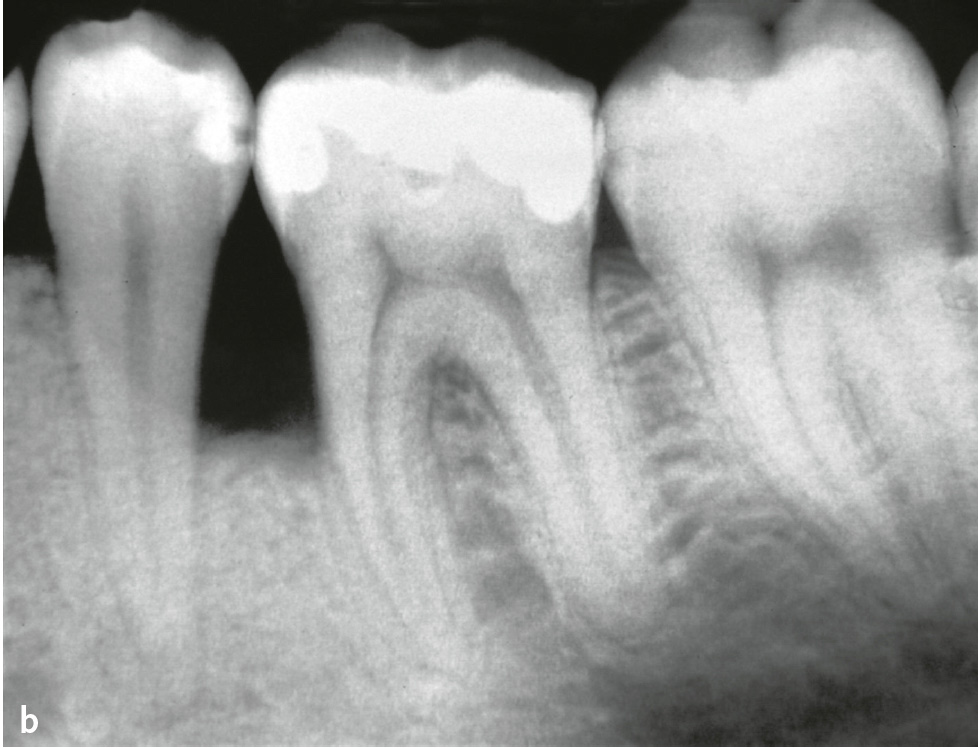

Eine weitere Ursache für isolierte tiefe parodontale Defekte sind vertikale Wurzelfrakturen wurzelkanalgefüllter Zähne (endodontal-parodontale Läsion mit Beschädigung der Wurzel: Wurzelfraktur; Tab. 1). Diese Frakturen können als Ermüdungsbrüche, verursacht durch zunehmende Versprödung der wurzelkanalgefüllten Zähne, als Folge zu starker Ausschachtung bei der Aufbereitung der Wurzelkanäle und daraus resultierender Schwächung der Zahnhartsubstanz bei normaler Belastung oder durch Traumata entstehen2. Reicht der Frakturspalt bis nach marginal, wird er bakteriell besiedelt. So kann es infolge dieser bakteriellen Besiedlung zur Zerstörung des Parodonts entlang des Frakturspaltes und zu einem isolierten tiefen Defekt kommen (Abb. 7).

Abb. 7 Vertikale Wurzelfrakturen: a) Zahn 25: intrakanaläre Stiftverankerung, vestibuläre Sondierungstiefe 9 mm, verstibuläre Fistel (oberer Pfeil), zwischen Gingiva und Kronenrand Frakturspalt sichtbar; b) Zahn 35: linguale Sondierungstiefe 10 mm, Frakturspalt sichtbar (Pfeile); c) Röntgenbild zu Abb. 7b mit Guttaperchaspitze im Fistelgang; d) Zahn 43: Wurzelkanalfüllung, Stiftkernaufbau, Beschwerden, perkussionsempfindlich, vestibuläre druckdolente Schwellung, Sondierungstiefe 11 mm, marginale Suppuration; e) Zahn 43 aus Abb. 7d nach Extraktion: Der Frakturspalt ist sichtbar, an dem entlang sich Konkremente nach apikal erstrecken.